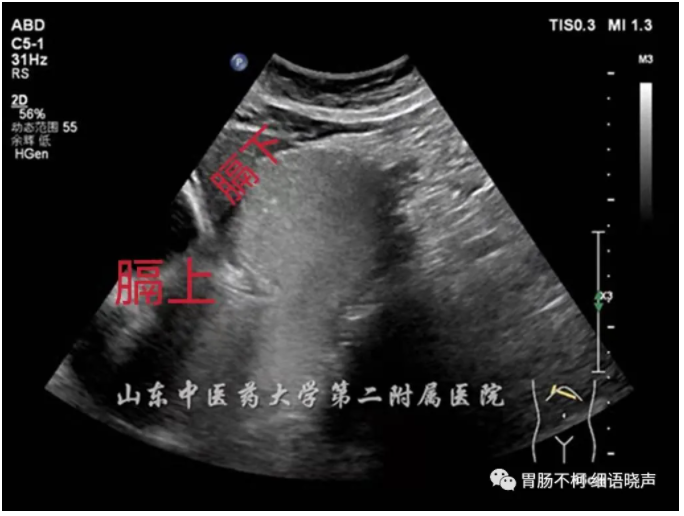

滑动型:EGJ上移,膈肌裂孔内径正常或增宽(正常解剖内经1.8-2.5cm),膈上疝囊及膈下胃呈“葫芦状”,“烧瓶状”,吸气、增加腹压、右侧卧位或二次充盈时疝囊及膈肌裂孔增大,造影剂在裂孔上下往返,膈上疝囊壁厚度及回声与胃壁一致相延续。

病例一,滑动型食管裂孔疝: